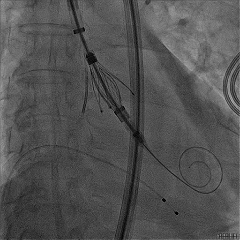

食道超声确认瓣叶夹持

经胸超声确认右冠瓣叶夹持

回撤MP导管,一键释放瓣膜

松弯后输送器回撤至大鞘,更换小鞘